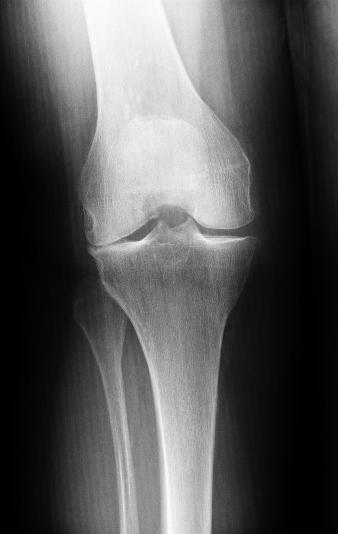

Die Kniearthrose betrifft nicht immer beide Gelenkhälften (Kompartimente) des Knies gleichzeitig. Der Knorpel kann in einem Teil des Knies bereits sehr abgenutzt sein, während er in einem anderen Bereich noch in gutem Zustand ist.

Man nennt die Arthrose des inneren Knies auch mediale Gonarthrose. Ist der äußere Anteil des Kniegelenks von Arthrose betroffen, spricht der Kniespezialist von einer lateralen Gonarthrose.

Laterale Gonarthrose entsteht insbesondere durch ausgeprägte Fehlstellungen der Beine (X-Beine). Durch die X-Fehlstellung lastet beim Stehen oder Gehen stets der größere Teil des Körpergewichts auf dem äußeren Knie. Der Knorpel nutzt sich an dieser Stelle entsprechend schneller ab.